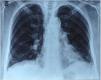

Thoracic CT angiography allowed us to eliminate a pulmonary embolism, and to objectify a diffuse bronchial syndrome in the form of regular circumferential bronchial wall thickening associated with sub-segmental atelectasis involving the internal segment of the middle lobe as well as the lower segment of the lingula, with ascension of the left diaphragmatic dome, without fibrosis (Figs. 1–3).

Evidence in favor of SLS was progressive dyspnea, ascension of the left diaphragmatic hemi-dome with basal band atelectasis and retracted appearance of the lung on chest CT, and restrictive syndrome on RFE. The non-reversible obstructive pulmonary involvement under bronchodilators with diffuse bronchial thickening on chest CT, and in the absence of smoking and atopy in our patient, suggests a priori a bronchial involvement of lupus.